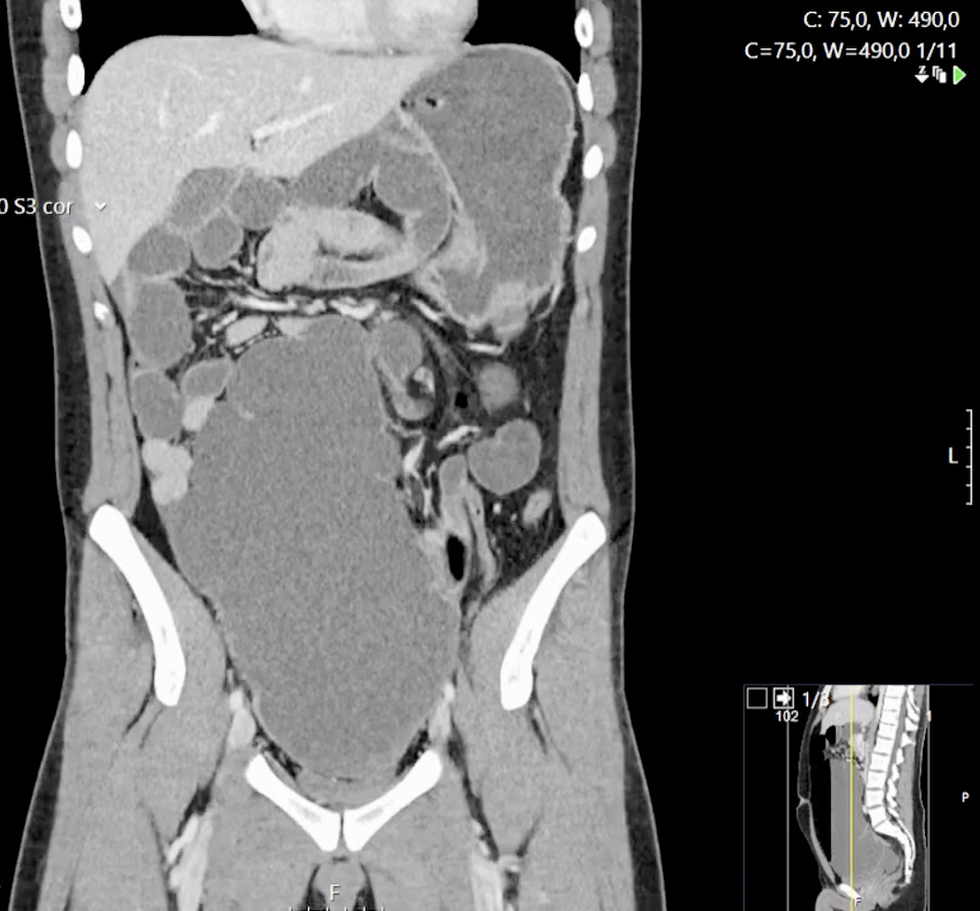

Figure 1 - Coronal CT image showing significant cecal distension and the ‘whirlpool sign’ due to twisted mesenteric vessels, suggestive of midgut volvulus.

Abdominal radiographs showed multiple air-fluid levels. Contrast-enhanced computed tomography (CT) of the abdomen and pelvis revealed marked cecal distension (13.5 cm), whirlpool sign indicating twisted mesenteric vessels and a malpositioned duodenojejunal junction and small bowel loops (fig. 1).

While plain radiography is of limited utility, cross-sectional imaging — particularly contrast-enhanced CT — plays a crucial role in adults. The “whirlpool sign” of twisted mesenteric vessels, malposition of bowel segments, and abnormal location of the duodenojejunal junction are pathognomonic findings (7). In this case, CT imaging was fundamental in achieving a timely diagnosis.